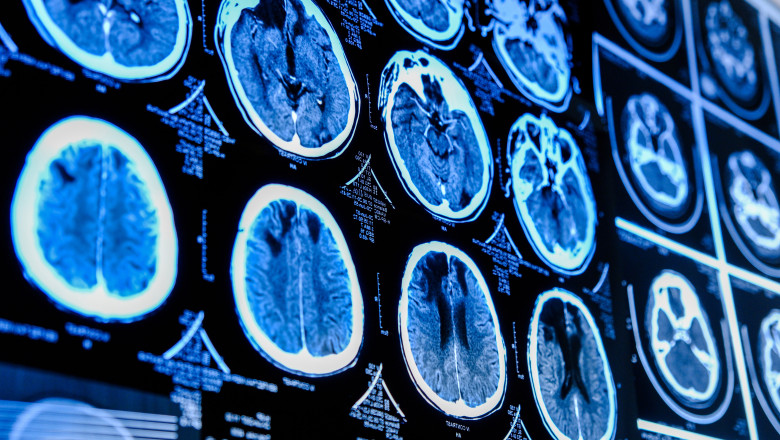

Pentru a cartografia îmbătrânirea cerebrală, Ali-Reza Mohammadi-Nejad, Stamatios Sotiropoulos, Dorothee Auer și echipa lor au utilizat modele de învățare automată, antrenate cu scanere cerebrale din Biobanca Regatului Unit de la 15.334 de participanți sănătoși, pentru a măsura diferența dintre vârsta cerebrală prevăzută a unui individ și vârsta sa reală, cunoscută sub numele de diferența de vârstă cerebrală.

Apoi, acest model a fost utilizat pentru a analiza două imagini RMN ale creierului la 996 de participanți sănătoși, realizate la un interval de cel puțin doi ani. În grupul de control (564 de persoane), ambele imagini RMN au fost realizate înainte de pandemie, în timp ce în grupul „pandemic” (432 de persoane), o imagine RMN a fost realizată înainte și cealaltă după începutul pandemiei.

Autorii au constatat că, la a doua scanare, efectuată aproape după trei ani, creierele participanților din grupul „pandemic” îmbătrâniseră în medie cu 5,5 luni mai repede decât cele din grupul de control. S-a observat o îmbătrânire cerebrală accelerată în perioada pandemiei, indiferent dacă participanții fuseseră infectați sau nu; cu toate acestea, infecția cu SARS-CoV-2 a fost asociată cu o creștere a ratei de accelerare pe măsură ce vârsta participanților creștea.